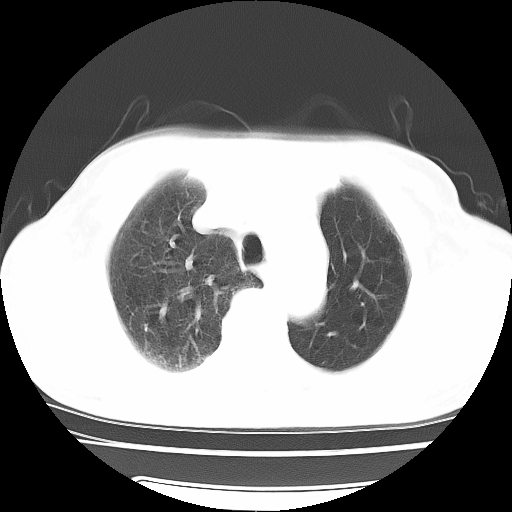

男,71岁,咳嗽,气喘10年,再发并咯血.胸片见气胸

考虑  左肺中心型肺癌伴阻塞性肺炎,肺不张,纵膈淋巴结肿大。慢支炎,肺气肿,左侧气胸肺压缩5%

左侧中央型肺癌伴纵膈淋巴结转移。

左肺中心型肺癌伴阻塞性肺炎,肺不张,纵膈淋巴结肿大

1)考虑左肺中心型肺癌伴阻塞性肺炎、左肺下叶肺不张、左侧肺气肿,纵膈淋巴结转移。2)左侧气胸(肺组织压缩约5%)。

左肺中心型肺癌伴阻塞性肺不张、肺气肿 。

1)考虑左肺中心型肺癌伴阻塞性肺炎、左肺下叶肺不张、左侧肺气肿,纵膈淋巴结转移。2)左侧气胸。